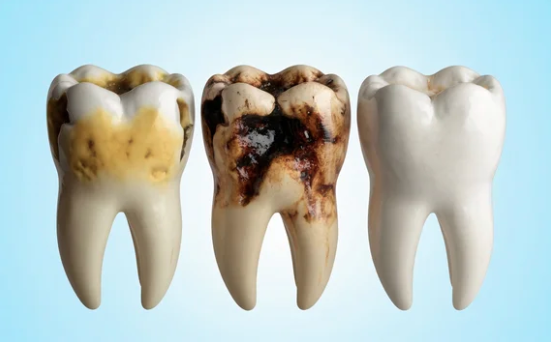

歯がほとんど残っていない方へ

「歯がほとんど残っていない」

• 歯がほとんど残っていない方